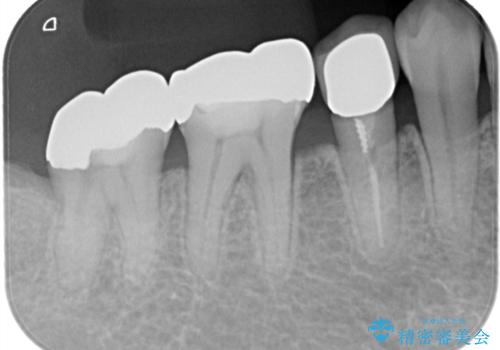

まずは銀歯を慎重に取り外し、歯の状態を確認しました。虫歯や劣化した部分は丁寧に除去し、必要に応じて土台を整えたうえで、セラミッククラウンを作製する準備を行いました。色や形は周囲の歯になじむように細かく調整し、自然な透明感やツヤを再現しました。

最終的には、左下5・6・7番の3本すべてをセラミッククラウンに置き換え。白くなったことで口元の印象が明るくなり、見た目だけでなく、かみ合わせも良好に仕上がりました。